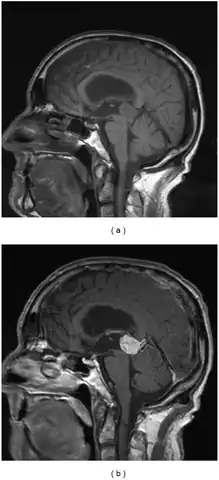

a,b)Parinaud's syndrome- sagittal and postcontrast sagittal images pineocytoma compressing the midbrain tectum

Cross section of midbrain. The area affected in Parinaud's syndrome is indicated by the striped region.